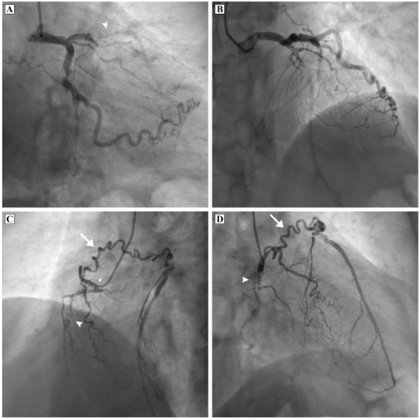

INTERESTING AND RARE ANGIO FOR FELLOWS. 75 year old male had STEMI, lysed in a nearby hospital. What is the finding?

Case of TOF with MAPCAS arising from coronaries and Dual LAD. My publication.

This set of clinical images depict the computed tomography #angiography of a 19-year-old male with a large non restrictive ventricular septal defect with severe pulmonary stenosis and aortic override suggestive of tetralogy of Fallot. https://t.co/Bmy5zOVyre